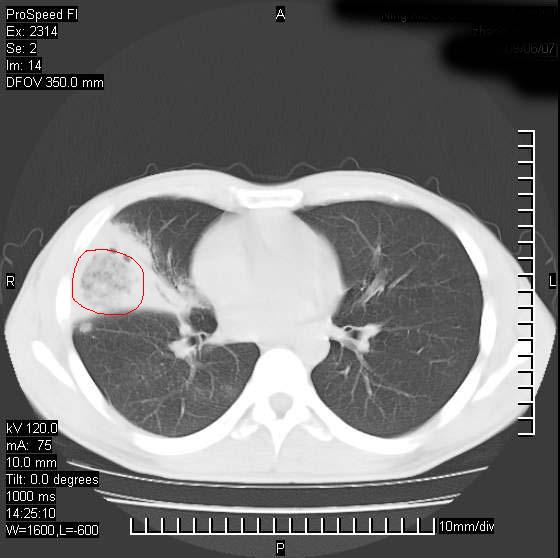

男性,再生障碍性贫血,入院前发热10天,最高40c,右侧胸痛,外院ct示右上,中肺边缘模糊的球性影(就是我现在图中标示的范围),考虑炎症,在我院使用头孢呋辛,洛美沙星10天,高烧消退,自感下午稍有发热,但今天ct示右上,中肺病灶明显扩大,还是考虑炎症,看其中的球型影是否霉菌感染??,是否能排除结核?

右肺中叶外侧段病变,上缘界限不清,下缘锐利,以段性发病为主,内见巨大空洞及空洞内容物,结合病史首先考虑:化脓性肺炎。不除外霉菌感染!

片状高密度影内见空洞影,内可见球形软组织密度影,并有新月征,考虑霉菌感染.